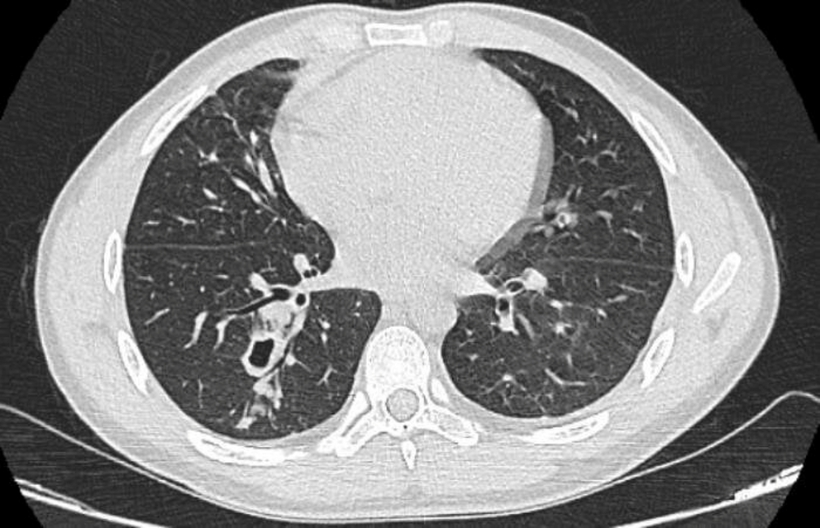

Hình ảnh phim chụp cắt lớp phổi của bệnh nhân nhiễm sán lá phổi. Ảnh: VTC News

Sán lá phổi có nhiều loài khác nhau (hơn 40 loài) nhưng có 2 loài thuộc nhóm sán lá phổi có mức độ gây hại nhất đó chính là Paragonimus heterotremus và Paragonimus westermani.

Tùy thuộc vào giai đoạn phát triển của bệnh cũng như các bệnh lý nền kèm theo mà mỗi người bệnh lại xuất hiện những triệu chứng bệnh khác nhau. Điển hình như rối loạn tiêu hóa, đau bụng dẫn tới tiêu chảy, tràn khí màng phổi hoặc tràn dịch màng phổi, ho kéo dài, ho khạc đờm có kèm máu, đau tức ngực, sốt nhẹ, cơ thể dần yếu ớt, khả năng hô hấp bị hạn chế.